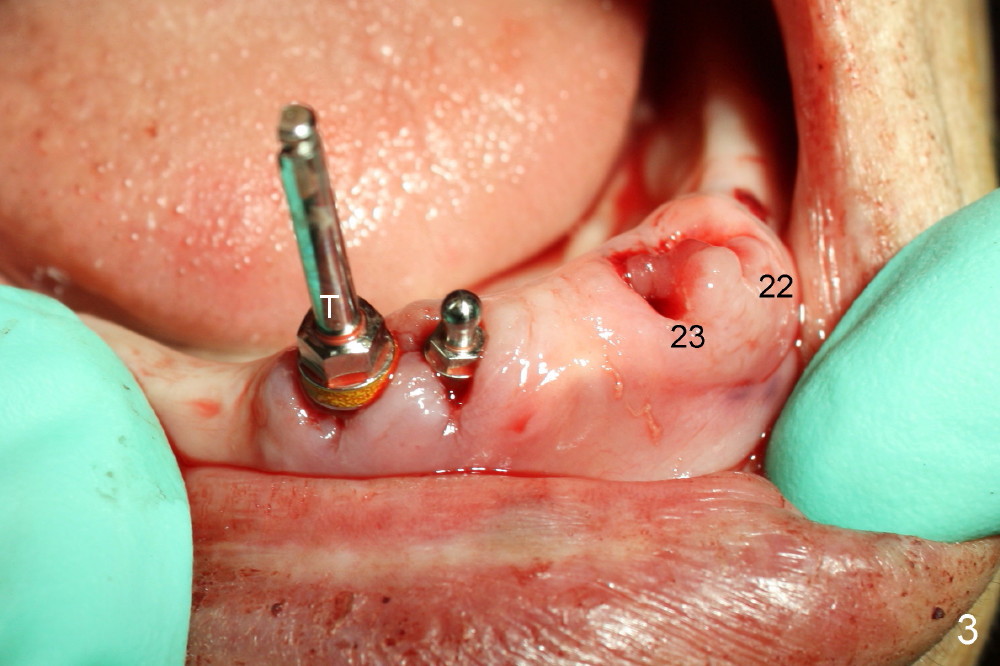

Following tooth extraction, the sockets are thoroughly debrided and packed with Clindamycin gauze (Fig.1: #22,23,26,27). PA is taken when 1.5 mm pilot drills are placed in the lateral incisor sockets and 2.0 mm in the canine sockets (Fig.2). Fig.3 shows that 4.5x17 mm tap (T) is placed in the lower right canine region, while 3.5x17 mm one piece implant is placed in the lower right lateral.